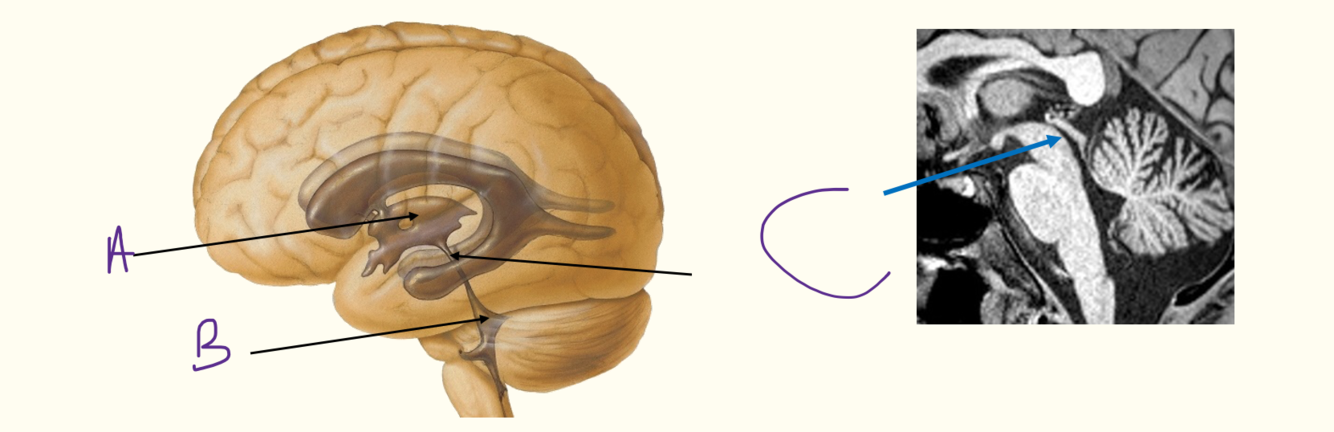

iv) label the diagram

iv) A = third ventricle

B = fourth ventricle

C = cerebral aqueduct

v) label picture A-G

v) A = midbrain

B = pons

C = medulla

D = cerebral aqueduct

E = sup medullary velum

F = fourth ventricle

G = inf medullary velum